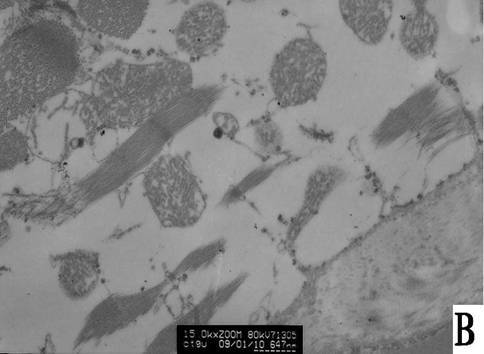

- 观察乌天麻(Gastrodia elata bl)对大鼠心肌缺血再灌注 I/ R 损伤的影响。灌胃给药14d后 ,进行Langendorff 离体心脏灌流 ,平衡、全心缺血(停灌)和再灌注各 30 min ,观察药物对左室发展压(LVDP)、冠状动脉流量(CF)、心肌组织超氧化物歧化酶(SOD)活力和丙二醛(MDA)含量以及超微结构的影响。乌天麻明显抑制 I/ R引起的LVDP和 CF的下降;提高心肌 SOD 活力和降低 MDA 含量 ,与模型组相比差异有极显著性意义P<0.01 ,但没有明显的量效关系 ;明显减轻 I/ R引起的心肌超微结构的损伤性改变。乌天麻对 I/ R引起的心肌损伤有明显的拮抗作用 ,其机制可能与其抑制自由基生成 ,改善能量代谢等有关。

- 目的:观察乌天麻(Gastrodia elata bl)对大鼠心肌缺血再灌注 I/ R 损伤的影响。方法:灌胃给药14d后 ,进行Langendorff 离体心脏灌流 ,平衡、全心缺血(停灌)和再灌注各 30 min ,观察药物对左室发展压(LVDP)、冠状动脉流量(CF)、心肌组织超氧化物歧化酶(SOD)活力和丙二醛(MDA)含量以及超微结构的影响。结果:乌天麻明显抑制 I/ R引起的LVDP和 CF的下降;提高心肌 SOD 活力和降低 MDA 含量 ,与模型组相比差异有极显著性意义P<0.01 ,但没有明显的量效关系 ;明显减轻 I/ R引起的心肌超微结构的损伤性改变。结论:乌天麻对 I/ R引起的心肌损伤有明显的拮抗作用 ,其机制可能与其抑制自由基生成 ,改善能量代谢等有关。